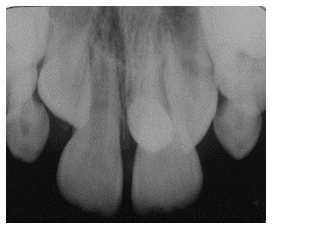

O diagnóstico de lesões de cárie dentária é uma das práticas

mais frequentes na clínica odontológica, com o objetivo de

detectar lesões de cárie precoce para, em seguida, fornecer o

tratamento menos invasivo. O exame visual e táctil geralmente

utilizado na detecção de cárie tem uma precisão limitada para

identificação de lesões não cavitadas, especialmente nas

proximais. Dentistas, portanto, usam regularmente exames

adicionais para ajudar na detecção, sendo a radiografia

interproximal (bitewing) provavelmente o mais frequente. Com

base no exposto, no que se refere ao diagnóstico clínico e

radiográfico de lesões de cárie, julgue os itens a seguir.

A detecção de cáries radiográficas é especialmente

adequada para identificar lesões dentinárias, portanto, é

útil no acompanhamento de lesões oclusais.Provas